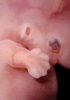

Carnegie Stage 18 (44 post-ovulatory days)

Most embryos at stage 18 are approximately 44 postovulatory days old and measure 13-17 mm in length. Distinguishing criteria for this stage include cervical and lumbar flexures, distinct notching in the hand plate, the first appearance of the elbow, eyelid folds may appear in more advanced specimens, and auricular hillocks begin to form distinct parts of the external ear.